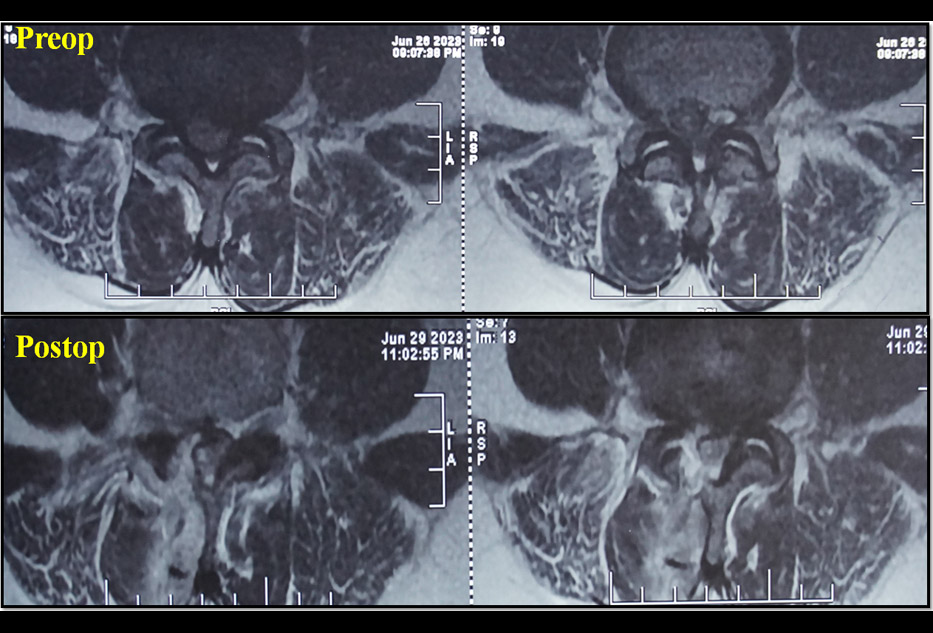

Cauda Equina Syndrome - 45 Yrs/M, with acute onset 5 days old h/o Cauda Equina Syndrome and a large superiorly migrated L4/5 disc as culprit.

Among many Endoscopic available options, I still found Destandau's technique a beautiful one in such scenarios.